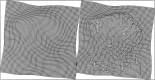

This paper describes a Bayesian method for three-dimensional registration of brain images. A finite element approach is used to obtain a maximum a posteriori estimate of the deformation field at every voxel of a template volume. The priors used by the MAP estimate penalize unlikely deformations and enforce a continuous one-to-one mapping. The deformations are assumed to have some form of symmetry, in that priors describing the probability distribution of the deformations should be identical to those for the inverses (i.e., warping brain A to brain B should not be different probablistically from warping B to A). A gradient descent algorithm is presented for estimating the optimum deformations.

Figures